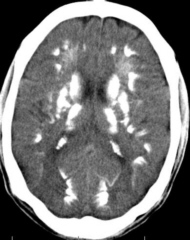

Fahr's Syndrome is a rare inherited neurological disorder that can present with a wide spectrum of symptoms, including those of Parkinson's Disease. It is characterised by abnormal deposits of calcium in areas of the brain that control movement, including the basal ganglia and the cerebral cortex. For more information go to Fahr's Syndrome

Symptoms of Fahr's Syndrome that are similar to those of Parkinson's Disease may include deterioration of motor function, dementia, dysarthria (poorly articulated speech), tremors, muscle rigidity, a mask-like facial appearance, shuffling gait, and a "pill-rolling" motion of the fingers. These symptoms generally occur later in the development of the disease.

More common symptoms of Fahr's Syndrome include dystonia (disordered muscle tone) and chorea (involuntary, rapid, jerky movements). The age of onset of Fahr's Syndrome is typically in the 40s or 50s, which is similar to Parkinson's Disease, although it can also occur at any time in childhood or adolescence.

Due to the possible similarity of symptoms to those of Parkinson's Disease, Fahr's Syndrome should be considered as an important differential diagnosis in cases of Parkinsonism. In order to refer to this article on its own click here